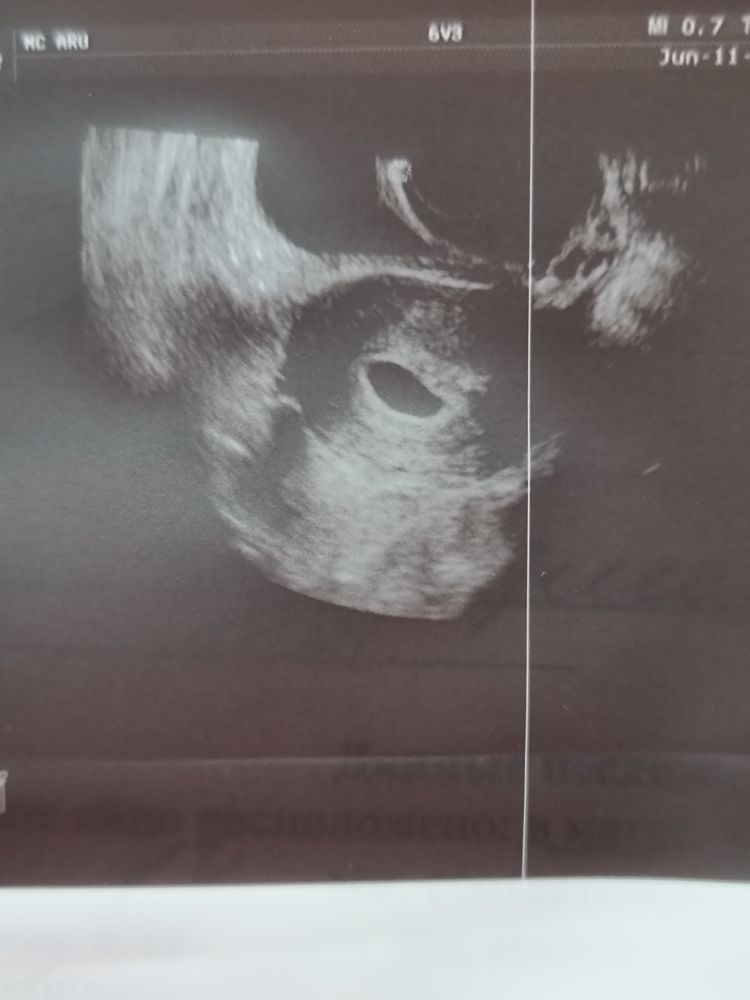

Ходила на узи, СВД плодного яйца 14 мм, соответствует 4-5 недель, (по календарю показывало 5 недель и 6 дней(акушерских))

Не жм, ничего не увидели

По среднему диаметру плодного яйца в 14 мм, это не 4-5 недель, а 3 недели и 6 дней. Еще никакого эмбриона, никакого желточного мешка не видно, они появятся к 5 неделям, когда СВД будет 21 мм.